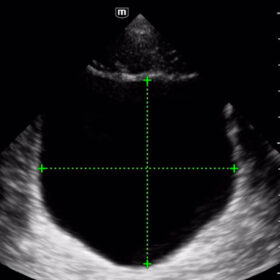

Mindray I3P WiFi Probe Image Gallery and Videos